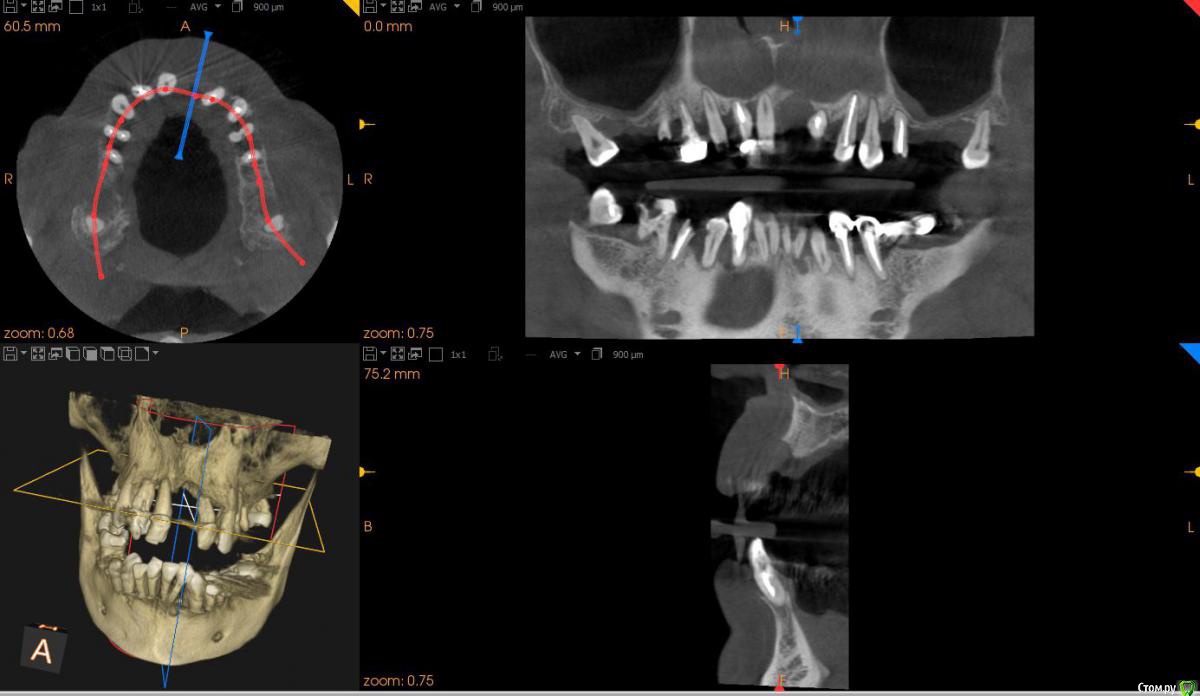

St. Опубликовано 17 апреля, 2018 Поделиться Опубликовано 17 апреля, 2018 Обзорные срезы ( верх, низ, топография нижнечелюстного нерва), дефект в обл 21 Ссылка на комментарий

kozloff Опубликовано 18 апреля, 2018 Поделиться Опубликовано 18 апреля, 2018 План действий.Удаление зубов.Повторное КТ.Рекомендуется костная пластика.Имплантация по шаблону. Ссылка на комментарий